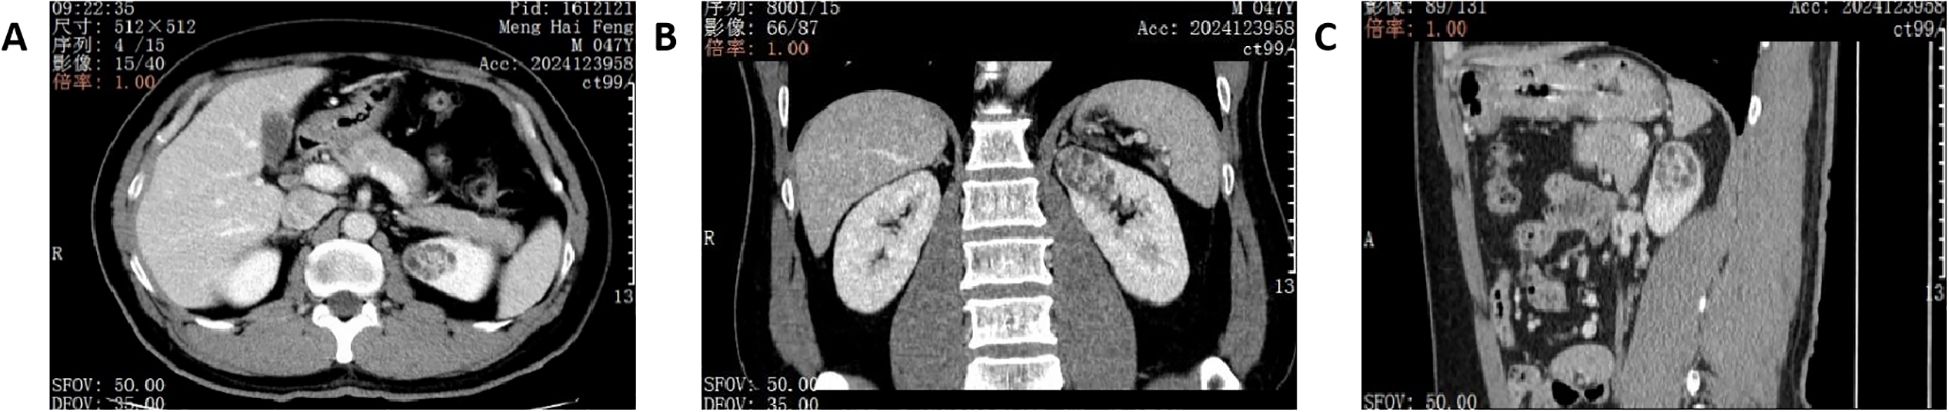

ELOC (also referred to as TCEB1)-mutated renal cell carcinoma (ELOC-mutated RCC) is a rare, molecularly defined RCC newly incorporated into the 2022 5th Edition WHO Classification of Tumours of the Urinary and Male Genital Organs 1. It exhibits a broad histomorphological spectrum with overlapping features with clear cell RCC, posing diagnostic challenges and potential for misdiagnosis if not considered. This report presents a case initially diagnosed as CK7-positive RCC with fibromyomatous stroma (RCC-FMS). Next-generation sequencing (NGS) revealed a ELOC p.Y79C gene mutation in tumor cells, leading to the definitive diagnosis of ELOC-mutated RCC. Enhancing awareness of this rare tumor is crucial for improving diagnostic accuracy.